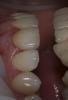

Art 7 Опубликовано 22 марта, 2013 Поделиться Опубликовано 22 марта, 2013 вкладка цирконпримерка до коррекции цвета,мне показалось что светлееи после корекции цветас какой стороны не посмотри, смотрится по разному.в реальности всё весма не плохо и я при разговоре и общении коронку абсолютно не замечаю 3 Ссылка на комментарий

pawa Опубликовано 23 марта, 2013 Поделиться Опубликовано 23 марта, 2013 да всё она жеНет блеска, смотрится как недополированная времяшка, портит общий вид. Ссылка на комментарий

Art 7 Опубликовано 23 марта, 2013 Автор Поделиться Опубликовано 23 марта, 2013 Нет блеска, смотрится как недополированная времяшка, портит общий вид.Посмотрите остальные фото, я специально попросил техника изобразить текстуру соседних зубов, мне кажется это удалось. С блеском проще всего, решил пробовать набирать опыта. Ссылка на комментарий